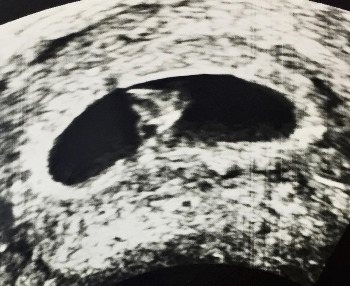

아기집 (Gestational Sac, GS)으로도 주수를 추정할 수 있지만 CRL을 사용하는 경향이 있습니다.

USG1.jpg 위 그림은 아기집 사진입니다. 이쁘죠? ㅎㅎㅎ

USG2.jpg 아기의 형태가 약간 보이긴 하나, 손가락 발가락 구별할 정도는 안됩니다.CRL을 측정할 수 있습니다.